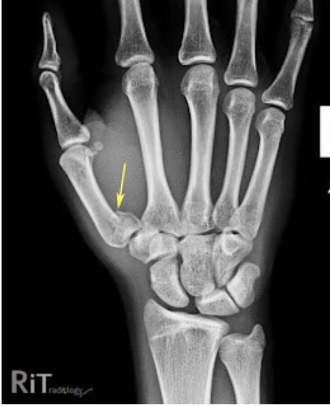

What is this fracture?

Boxer

What is boxer fracture?

Fracture of distal fifth metacarpal

Results from punching someone or something